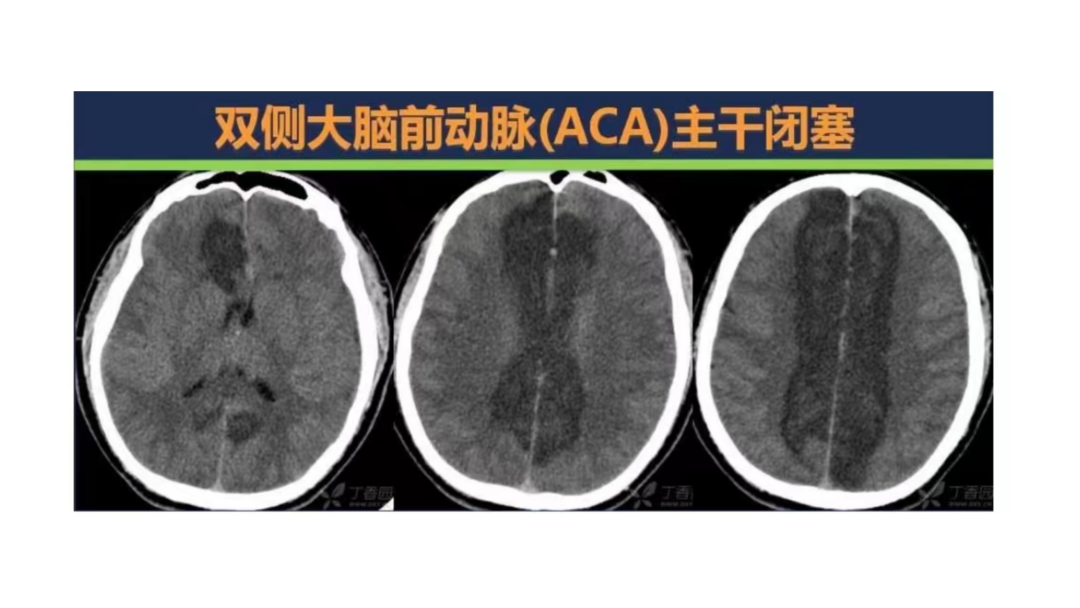

小血管血栓取栓病例

注:本文内容由赵宝元整理,其中部分病例作者详见下文。

作者:江苏泰州丁鸭锁、孙兵、尹春等。